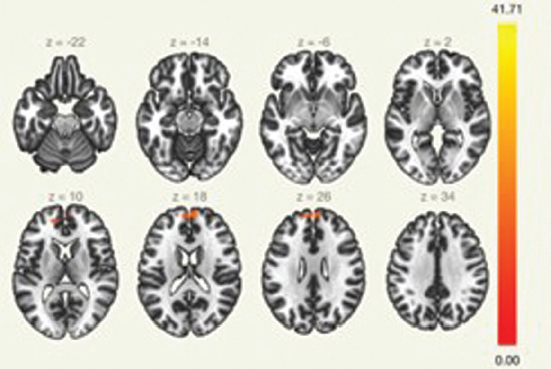

Оценка изменения функциональной коннективности при межгрупповом сравнении по отношению к данной сети показало увеличение кластеров в префронтальной области у пациентов группы № 1 (группы с удачным исходом трансплантации), что может свидетельствовать о восстановлении связей в данной нейросети за счет пула зеркальных/молчащих нейронов префронтальной области.

Увеличение функциональной коннективности верхних лобных извилин с обеих сторон (рис. 1), а также диффузно в области лобных долей, влечет изменения клинической картины: снижение выраженности уровня аффективных расстройств у пациентов, улучшение результата в тестах SDMT (тест символьно-цифрового кодирования).

Рис. 1. Кластер № 1 сети пассивного режима

Fig. 1. Cluster N 1 of the default mode network